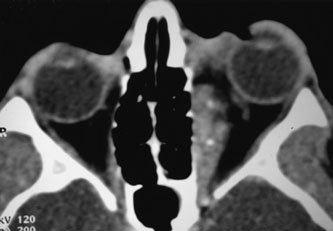

Investigations

If NFM is suspected, MRI should be ordered of the orbits and brain to exclude noncontiguous intracranial anomalies.93 Magnetic resonance imaging demonstrates the dilated cystic spaces with either a hypointense (lymphatic cyst) or hyperintense (hemorrhagic cyst) signal on T1-weighted images, and a hyperintense signal on T2-weighted images (Fig. 10, A&B).94Layering may be seen within the cysts if there has been a recent hemorrhage leaving unresorbed blood. The CT scans of patients with a deep NFM show low-density, poorly defined masses behind the orbital septum in the extraconal and intraconal spaces, which may indent the globe.3 Calcification within the mass (Fig. 11) and inhomogeneous enhancement of the rim and focal areas within the lesion may be seen that corresponds to abnormal endothelially lined channels.3 Enlargement of the bony orbit can occur, particularly with combined lesions.3,89 If the diagnosis is still unclear, ultrasonography can be performed. A cystic orbital mass is seen on B-scan. A-scan shows features of a solid, cellular tumor: low reflectivity, regular homogeneous internal structure, and marked sound attenuation through the mass.3,89 Standard pulsed Doppler ultrasound confirms no intrinsic flow within the lesions.

Fig. 11. Axial computed tomography scan of patient in Figure 9, showing poorly defined orbital mass with calcifications. (Courtesy of Nancy A. Tucker MD, Illinois Oculoplastic Associates)